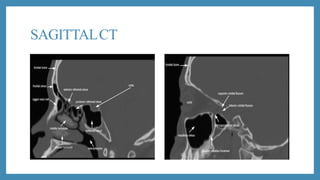

SAGITTALCT

CT scan

 CT scans: Excellent views of the sinuses, best for osteomeatal

complex and ethmoidal disease

 “Limited CT Evaluation” – slice 3-4 mm

 CT navigation:

 A computer is used to identify the 3- dimensional location of a

probe tip placed within the patient's nose or sinuses..

 Improves anatomical identification and avoid damage to vital

neighbouring structures such as the brain and eyes.